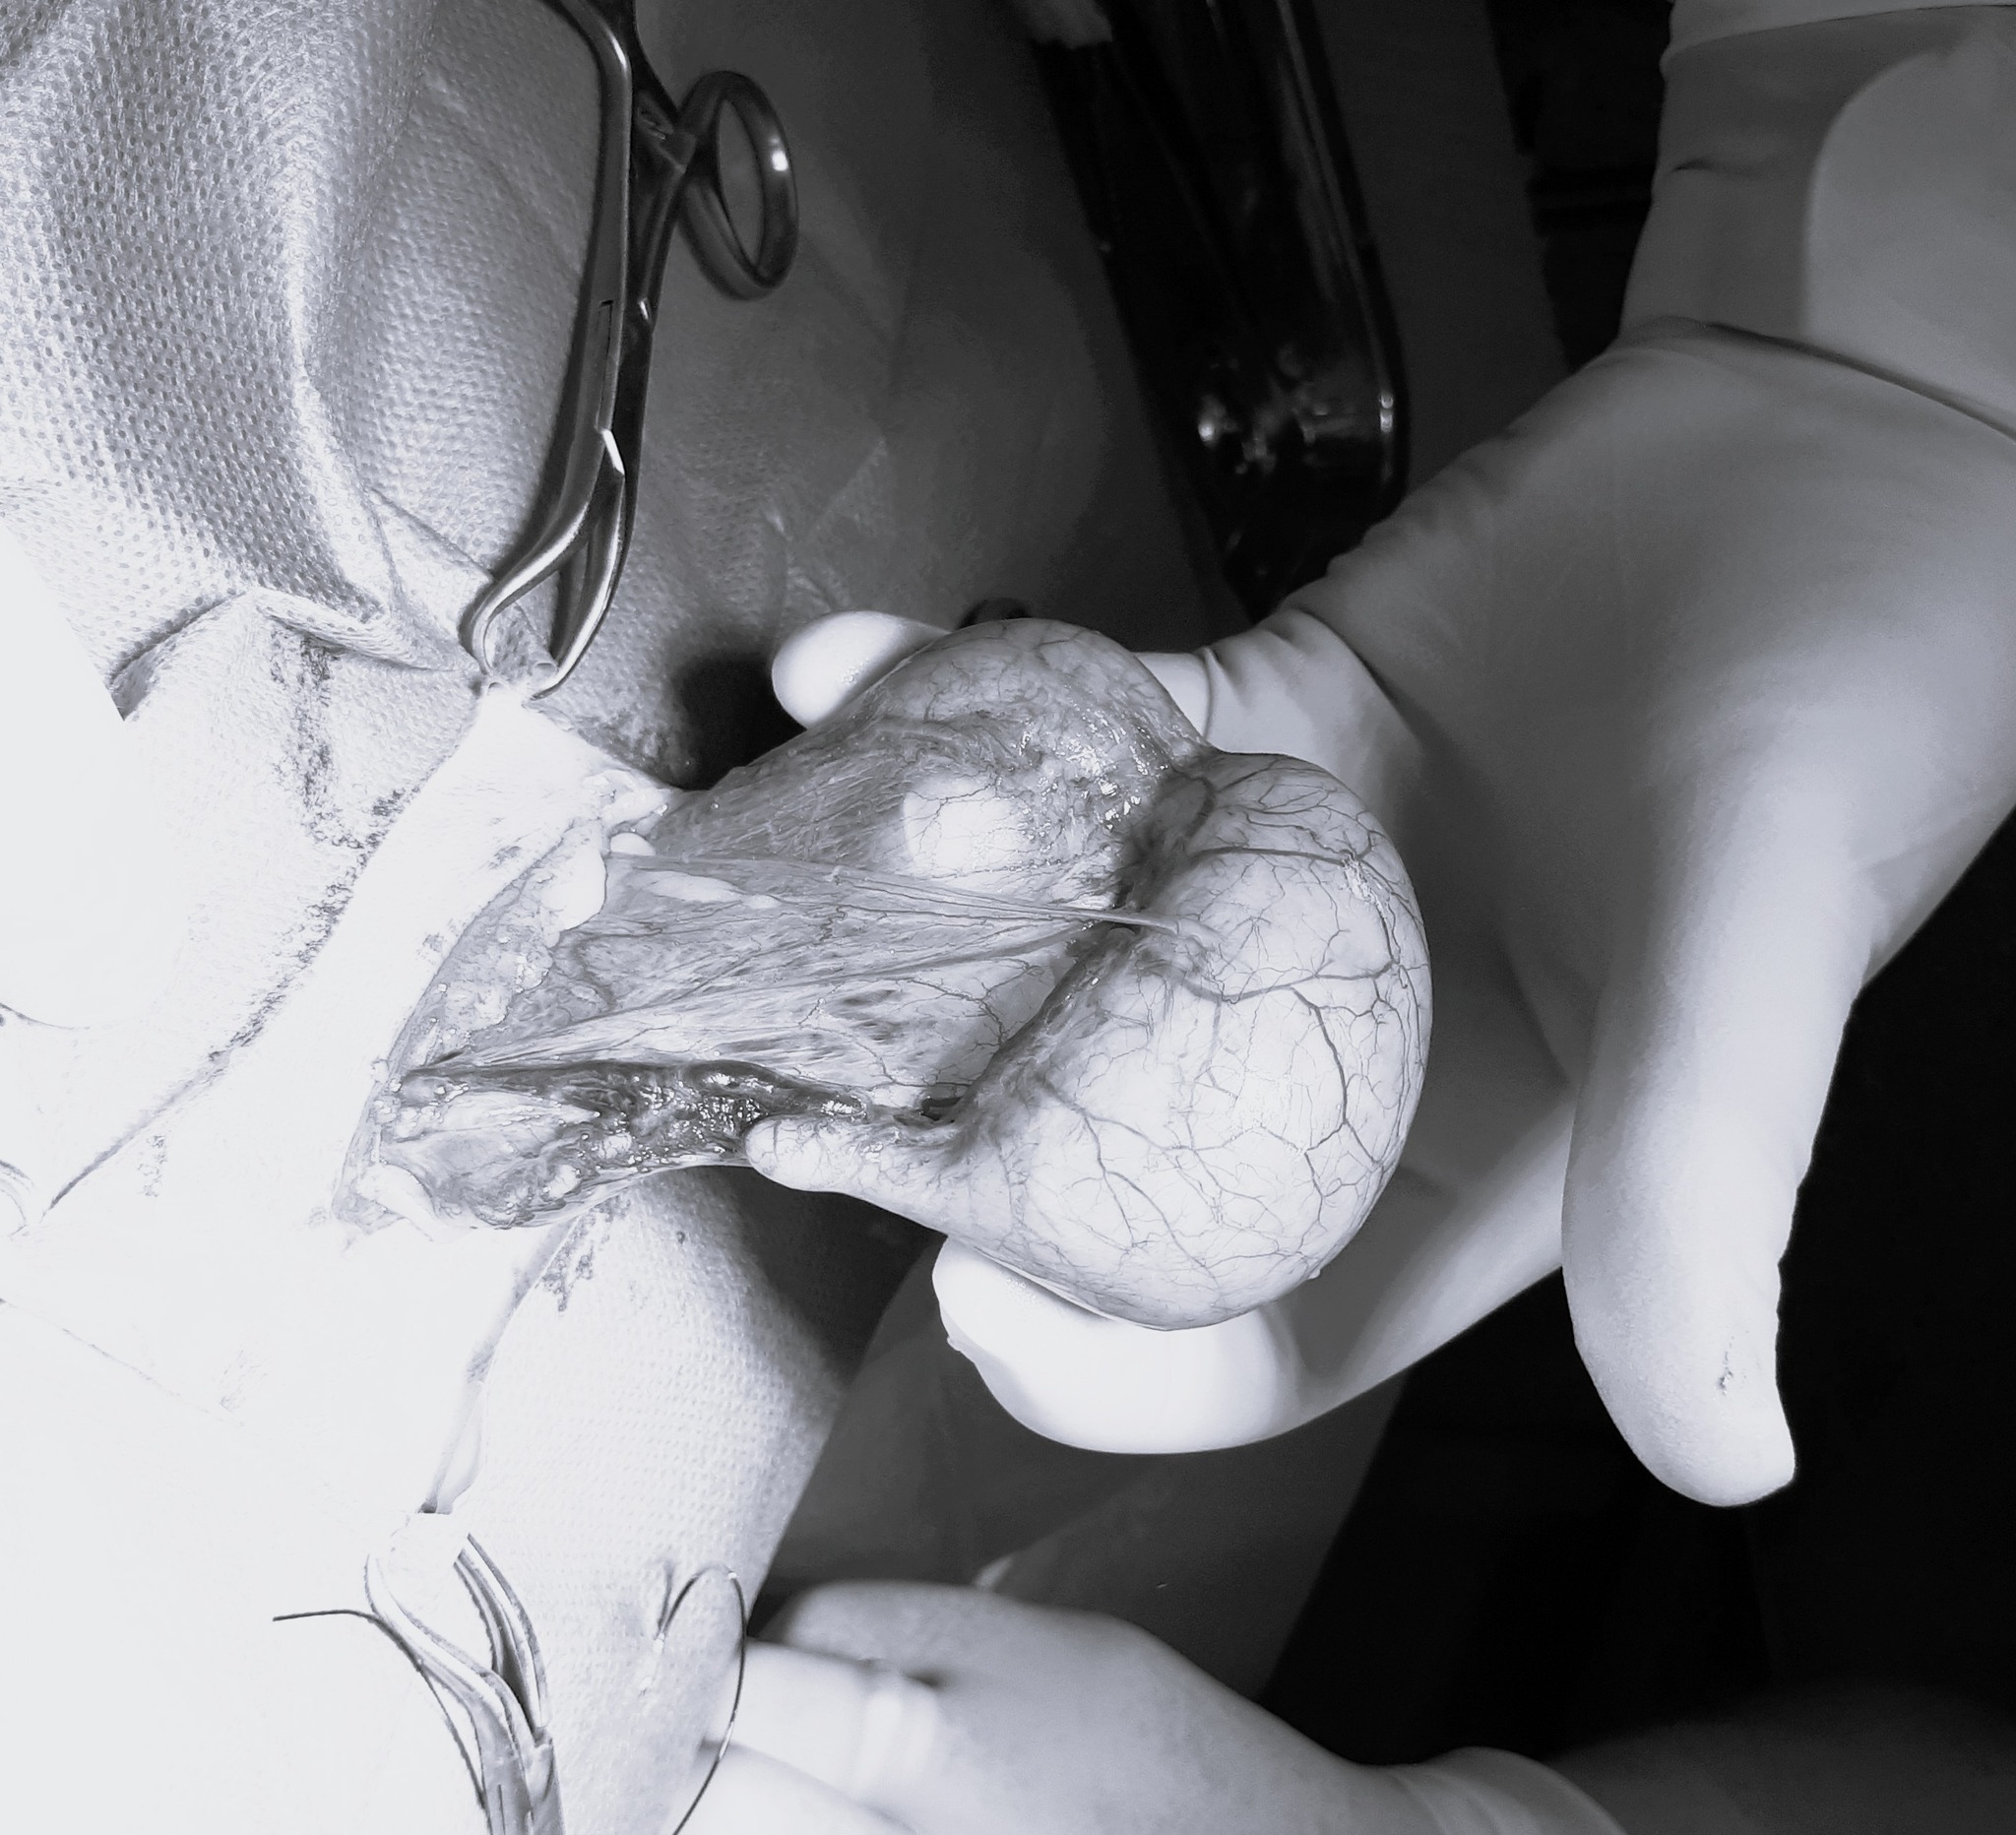

ZobaczTo był trudny i niezaplanowany poród ale mamy to!!!